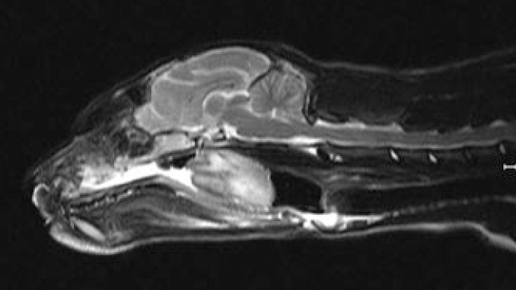

Все о том как делают МРТ собаке

Услуги по проведению МРТ собаке предоставляют только несколько специализированных ветеринарных клиник города Санкт-Петербург. Спрос на такую диагностику растет с каждым днем. Наши домашние питомцы точно...